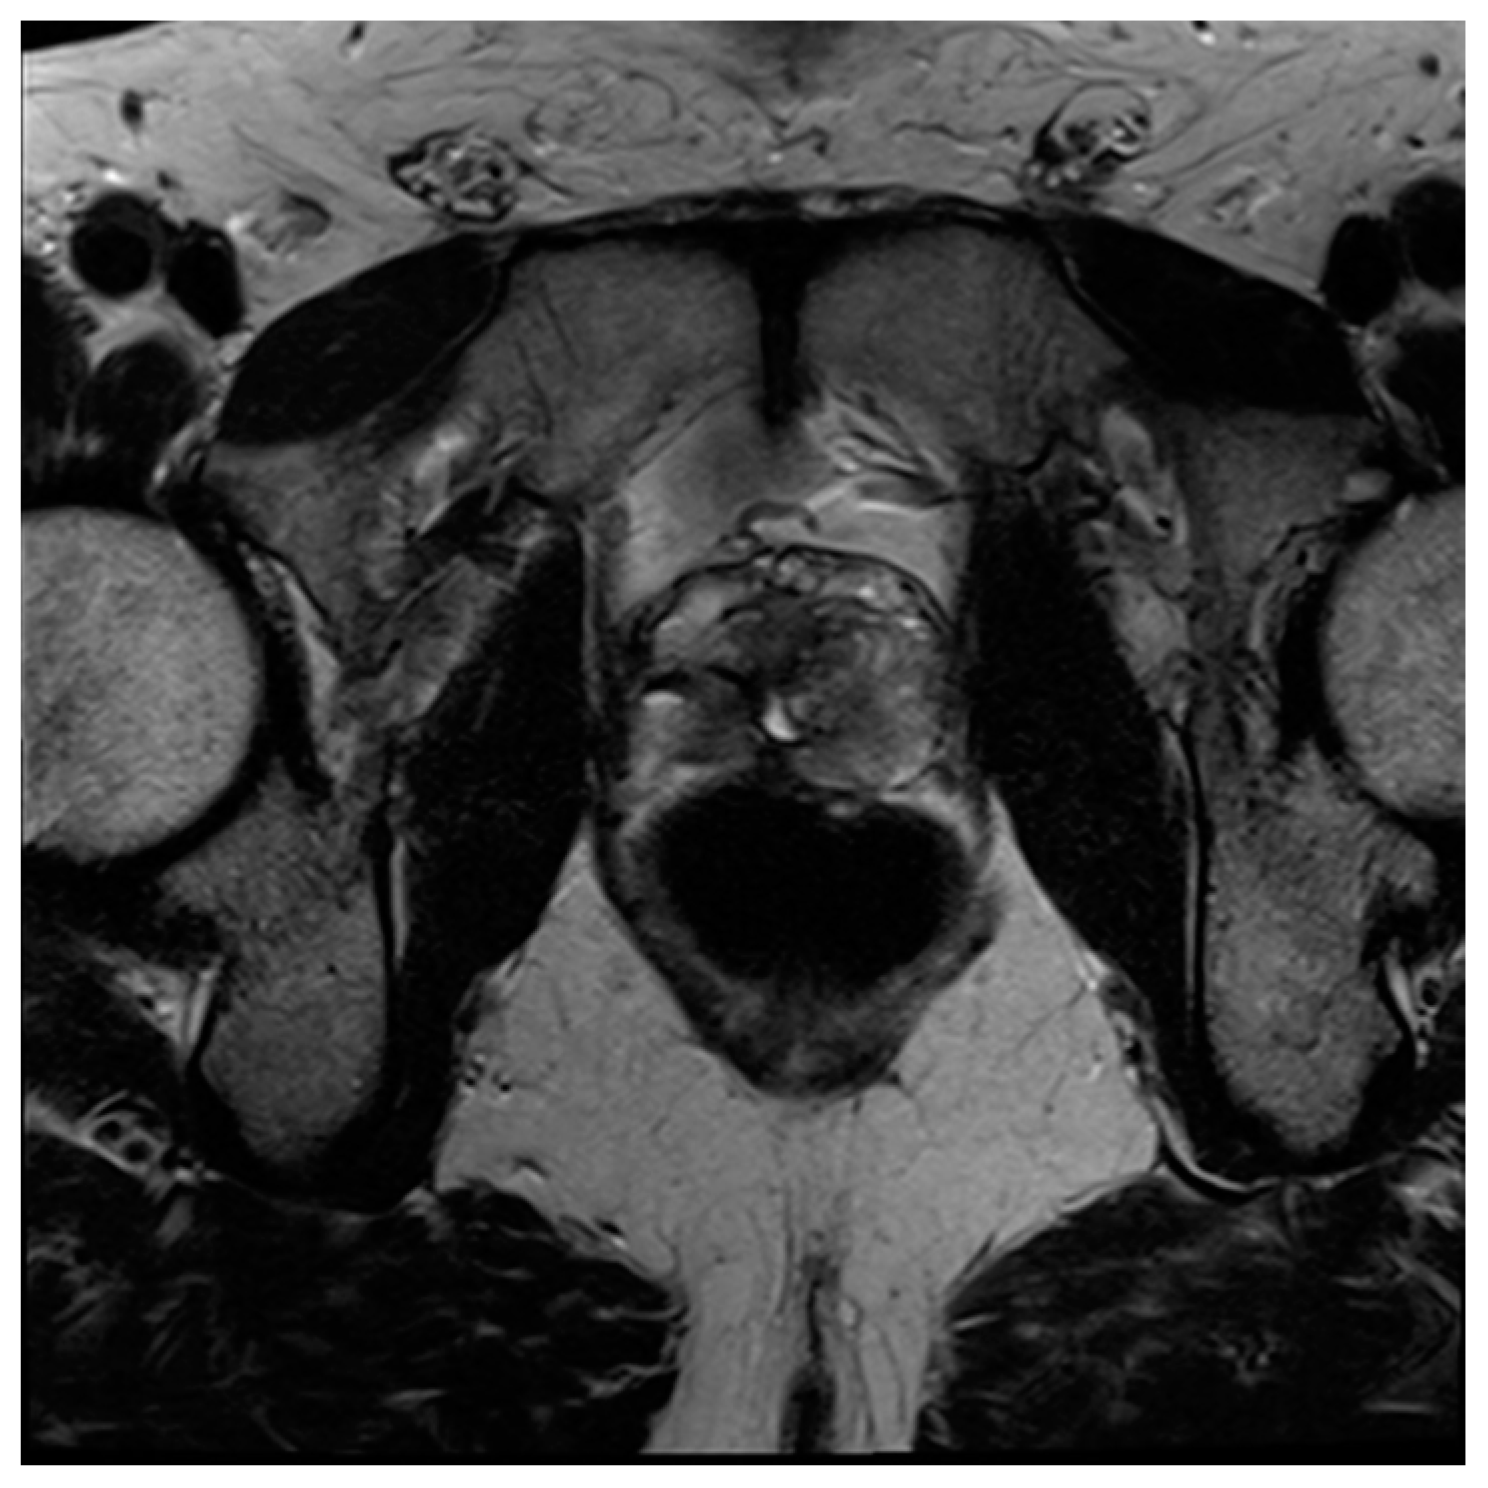

Figure 1. Axial CT image of the pelvis following the administration of intravenous contrast demonstrates focal asymmetric enhancement of the left seminal vesicle, subsequently found to represent prostate cancer at the time of biopsy.

It is widely accepted that CT is insufficient for the diagnosis and monitoring of prostate cancer within the gland due to its inferior soft tissue characterization [6]. The relatively high radiation dose associated with this modality also limits its use as a screening tool. However, although other modalities outperform CT in the diagnostic workup of prostate cancer, it may still have a role. Additionally, with the emerging field of radiomics, additional information can be extracted from CT scans that is not readily apparent in conventional imaging [7,8]. Due to the fact that CT scans are so widely available and frequently performed, familiarity with the appearance and limitations of prostate imaging using CT is useful in order to maximize incidental detection of cancers and inform possible next steps [9]. The ability of CT to identify prostate malignancy depends greatly on the location of the lesion within the gland, as BPH nodules within the transition zone are largely indistinguishable from cancers. For example, in one study, helical CT accurately revealed 58% of the cancer sites in the peripheral zone, whereas nodules in the transition zone were indistinguishable from benign change [10]. Another study showed that although CT was insensitive for the detection of prostate cancer (17.4%), when lesions were considered highly suspicious when using CT, it was 98% specific for malignancy, adding further evidence that suspicious CT lesions warrant further investigation [9]. Additionally, of twenty MRIs with lesions suspicious for clinically significant prostate cancer, fifteen had an accompanying CT correlate of focal intraprostatic hyperenhancement (Figure 1) [5].